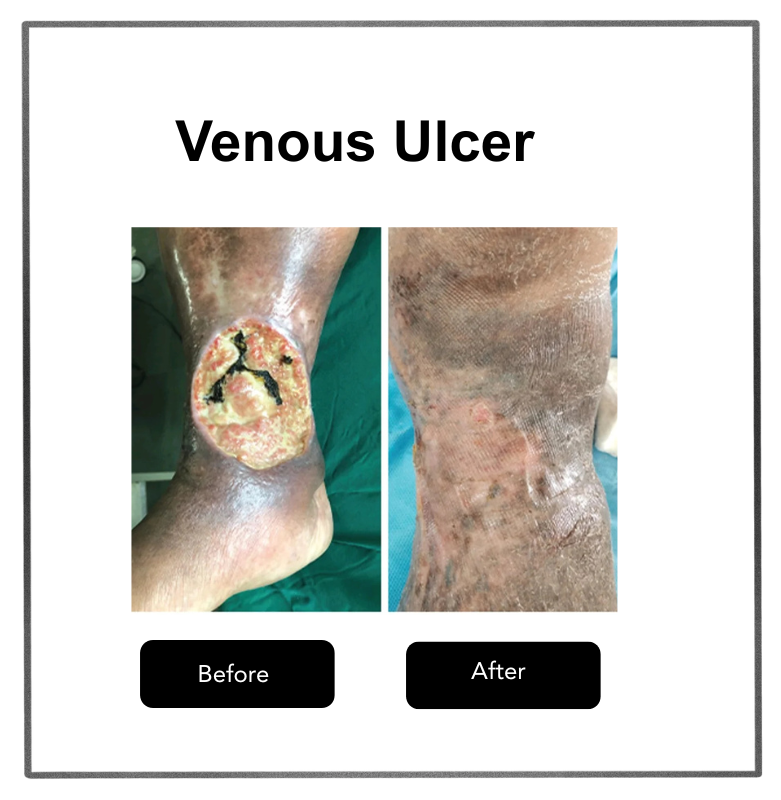

Poor circulation and high blood sugar create an environment prone to infections and impaired healing. If left untreated, these injuries can turn into non-healing ulcers and, in severe cases, lead to gangrene (black foot), where tissue dies and amputation may be necessary.

Discover how minimally invasive treatments help relieve pain and improve the appearance of legs.